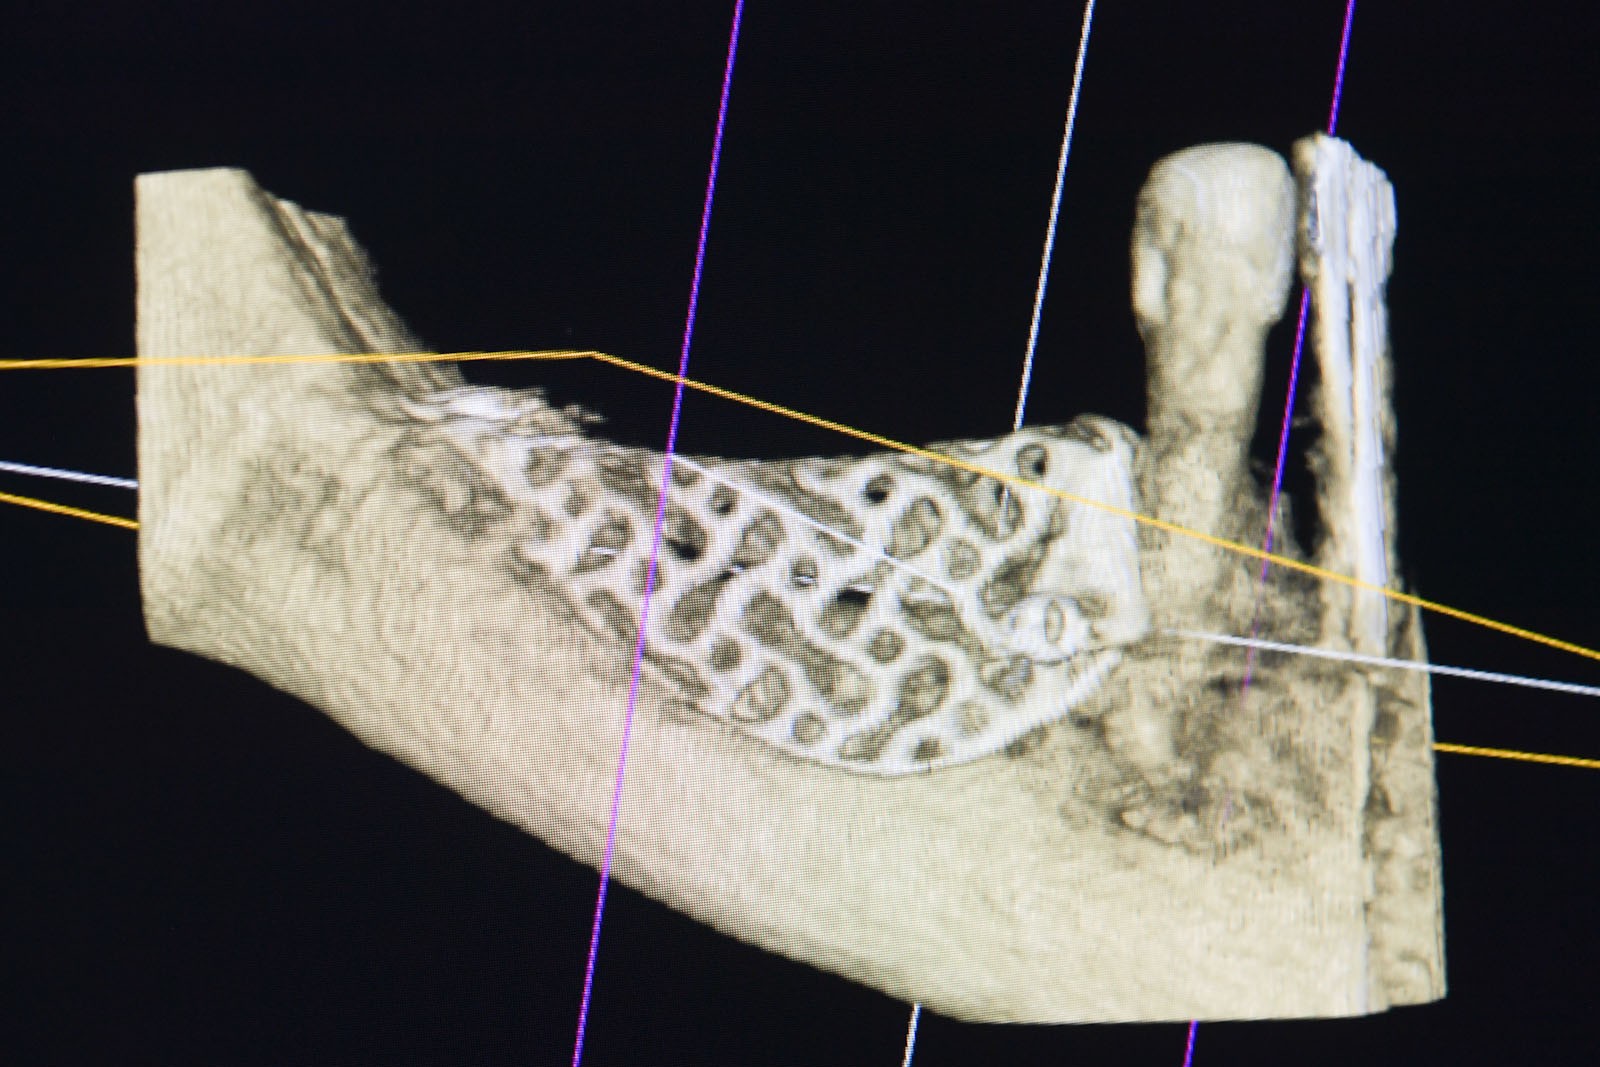

To kolejna metoda umożliwiająca precyzyjną odbudowę zadanego kształtu tkanki kostnej przy użyciu standardowych materiałów kościotwórczych, kości własnej lub PRF oraz zewnętrznego rusztowania w postaci siatki z biozgodnego stopu tytanu. Siatka jest indywidualnie projektowana w technologii CAD CAM i następnie drukowana dla konkretnego przypadku.

Dotychczas stosowane stabilizatory zewnętrzne w formie siatek tytanowych używane do regeneracji kostnej lub w zabiegach odtwórczych w chirurgii szczękowo-twarzowej uwzględniały materiały ręcznie doginane i formowane podczas zabiegu operacyjnego. Zastosowanie technologii CAD CAM dla potrzeb druku materiałów przeznaczonych do indywidualnej rekonstrukcji kostnej znacznie poprawiło precyzję i jakość uzyskiwanych efektów. Wdrożenie biozgodnych stopów tytanu do druku siatek zdecydowanie ograniczyło odsetek powikłań zapalnych.

Siatki stanowią stabilną obudowę – ograniczenie nadające kształt regenerowanej kości przy użyciu upakowanego pod nią materiału. Utrzymują i stabilizują rozdrobniony granulat kościotwórczy, co jest warunkiem prawidłowego procesu gojenia, jednocześnie nadając anatomiczny kształt i zakres odbudowie kostnej sprzed jej zaniku.

Precyzja projektu druku siatki bazuje na dokładności odwzorowania kształtu kości w stożkowej tomografii komputerowej CBCT, co zapewnia ich dobre przyleganie do podłoża kostnego oraz ogranicza powstawanie powikłań w postaci obnażania się siatek.

Precyzja projektu oraz materiał, z którego wykonana jest siatka (biozgodny stop tytanu), powodują, że obnażenie się siatki nie zaburza procesu gojenia i regeneracji kostnej. Wymaga jedynie większej ilości kontroli pozabiegowych oraz wzmaga czujność higieniczną zarówno ze strony lekarza, jak i pacjenta.

Ten rodzaj odbudowy kostnej stosowany jest w sytuacjach złożonych, trójwymiarowych 3D ubytków kości, przy których standardowe metody odbudowy są niewystarczające. Ilość kości, którą możemy uzyskać, stosując tę metodę, to nawet kilka centymetrów sześciennych.

Metoda rekonstrukcji kostnej w oparciu o indywidualnie drukowane siatki z tytanu dla implantacji wszczepów śródkostnych stosowana jest najczęściej jako dwuetapowa. W pierwszym etapie odbudowywana jest kość, natomiast implanty wszczepiane są po okresie 4–6 miesięcy. Na wgojenie implantów oczekujemy od 4 do 6 miesięcy w zależności od miejsca ich lokalizacji. Siatka tytanowa po spełnieniu swojej funkcji rusztowania dla odbudowującej się kości jest następnie usuwana w dniu wszczepienia implantu. Jeżeli kość spełnia odpowiednie warunki, istnieje możliwość zastosowania modyfikacji siatki tytanowej, która umożliwia jednoczesne wprowadzenie implantów wraz z odbudową kostną. Wariant ten skraca czas od pierwszego zabiegu do wykonania gotowych koron protetycznych na wprowadzonych implantach.